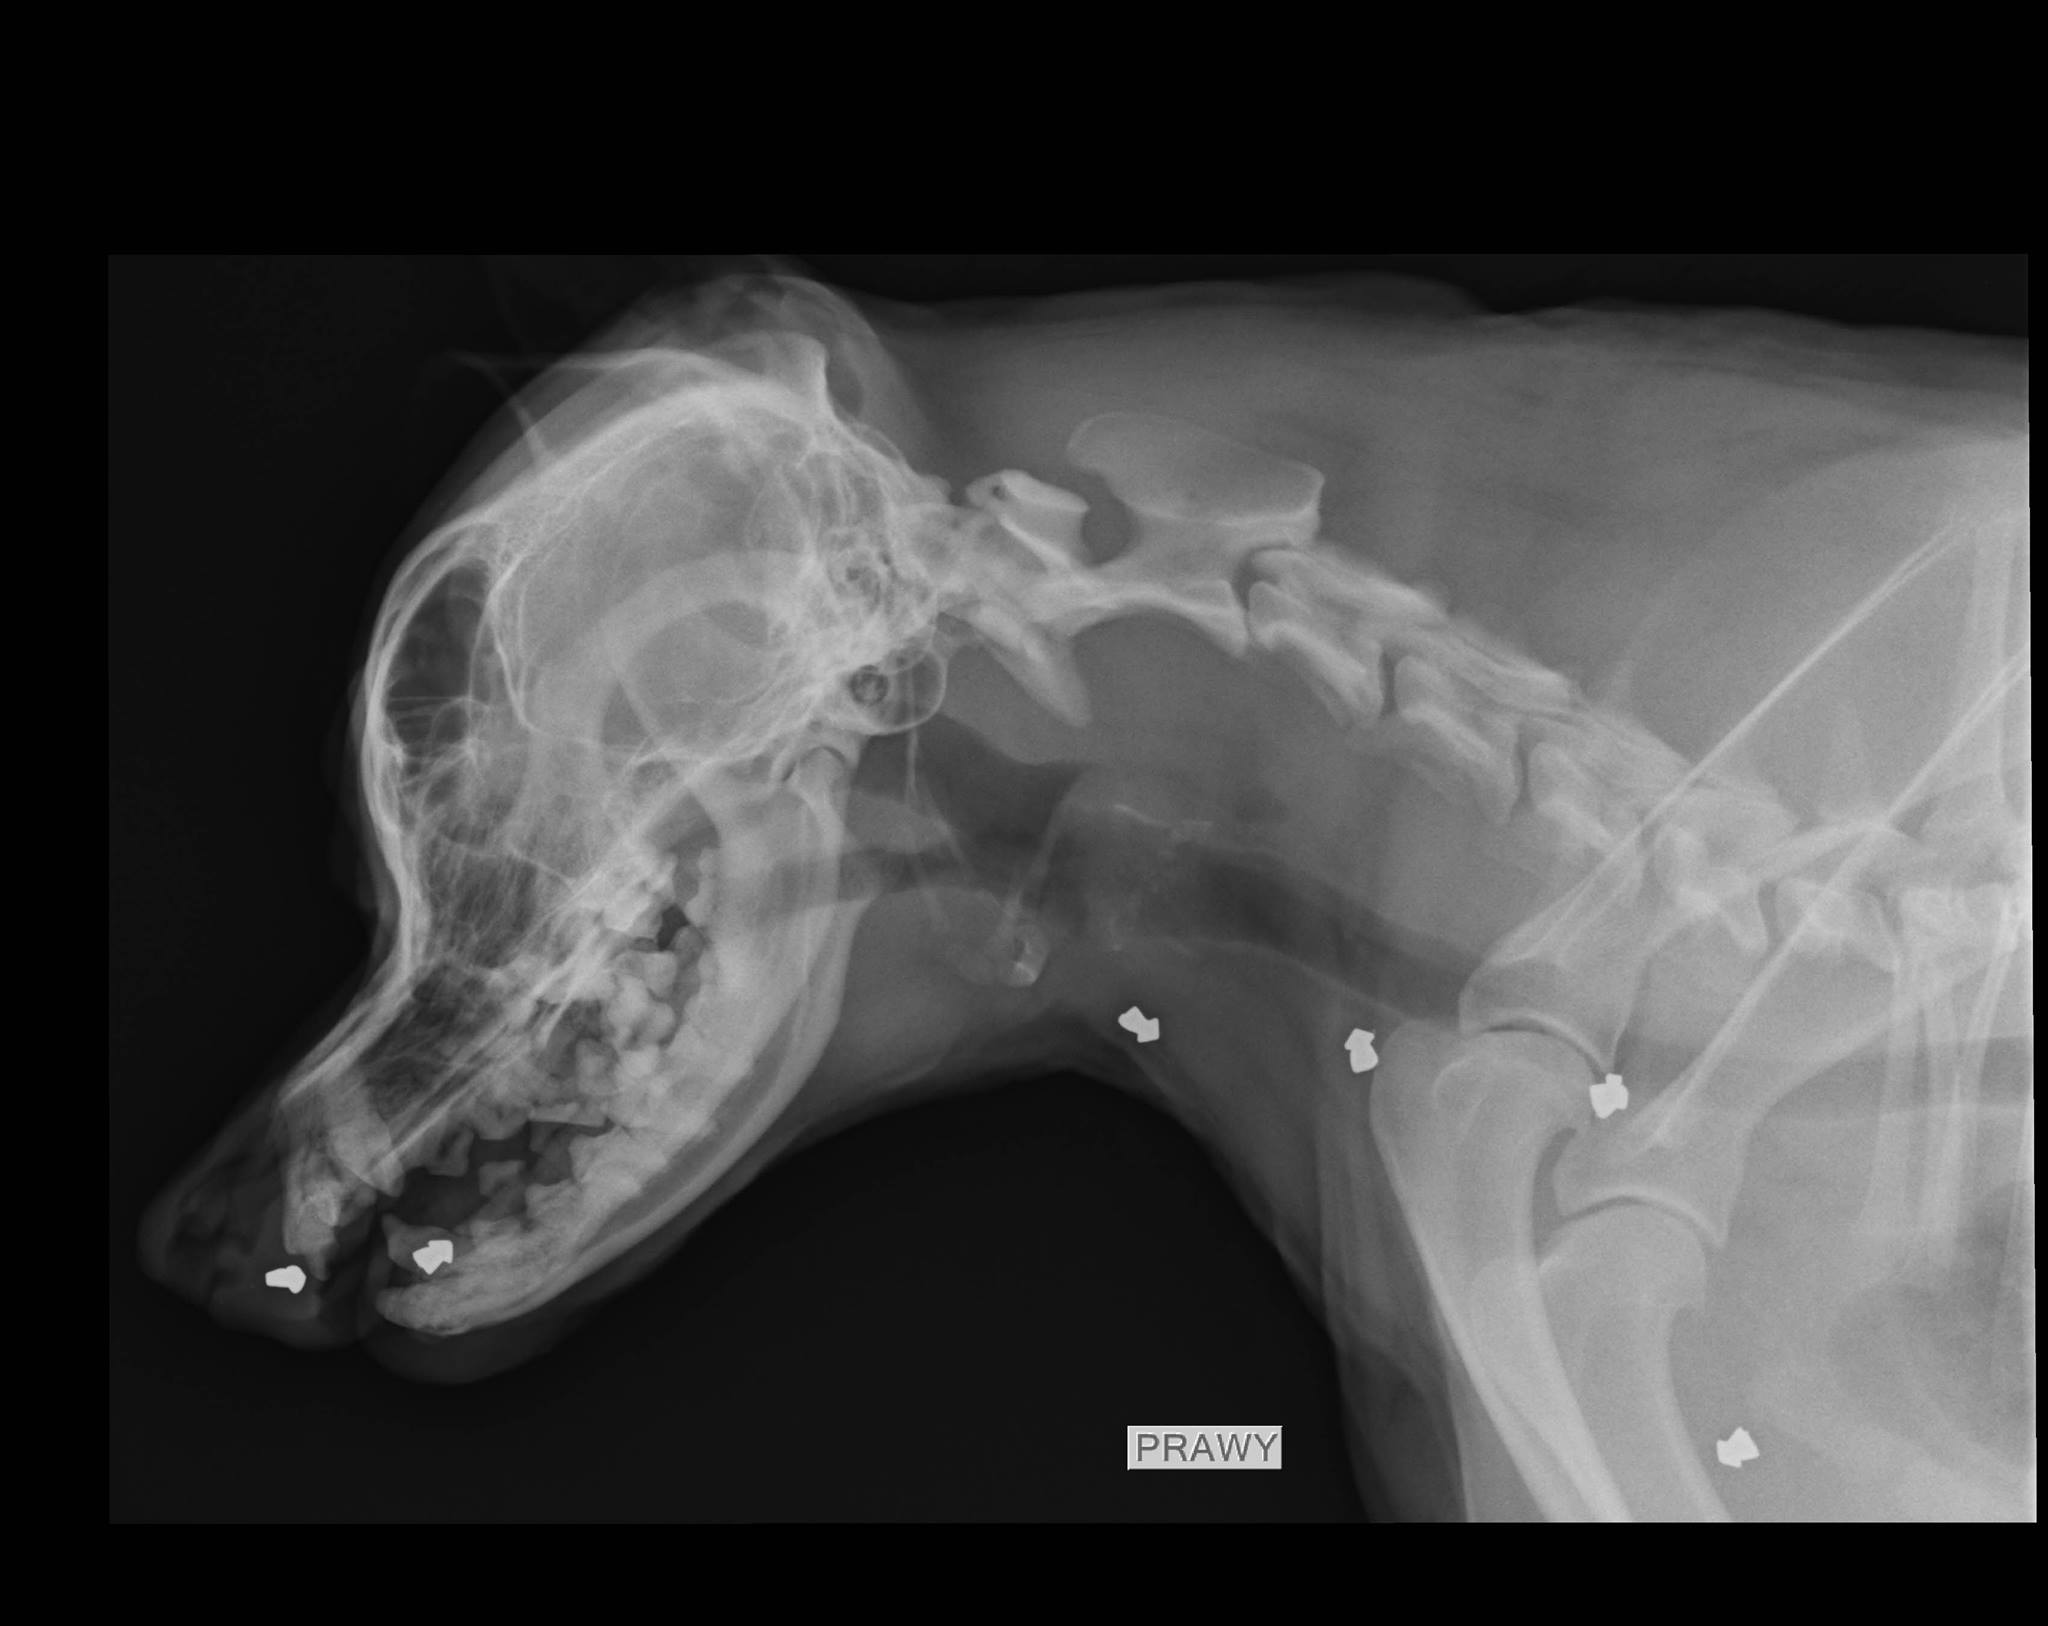

Godzina 16:30, do Centrum Weterynaryjnego wchodzi dwóch strażników miejskich z kontenerkiem do transportu zwierząt. Kolejny powypadkowy, bezpański nieszczęśnik potrzebuje pomocy. Strażnicy stawiają kontenerek na stole do badania. W środku przerażone i zdezorientowane zwierze, kocur w wieku około 5 lat. Ma tylko pół lewego ucha, 1/3 ogona i złamany kieł żuchwy. Jako bezpański, dziki kot nie raz musiał dostać łomot. Kocisko przeraźliwie zawodzi. Pomimo tego, że moi pacjenci raczej ze mną nie gadają, ciężko jest nie zrozumieć kociego błagania o pomoc. Podczas badania okazuje się, że cała okolica krocza jest wylizana do „żywego mięsa”. Pęcherz moczowy jest wielki i bardzo twardy, w dotyku zupełnie nie przypomina zdrowego kociego pęcherza. Następne pół godziny i mamy wynik badania USG i zdjęcia rentgenowskie. Diagnoza? Atonia i potworne zapalenie pęcherza moczowego będące skutkiem… postrzału z wiatrówki. W pęcherzu moczowym tkwi ołowiana śrucina. Tkwi tam już całkiem długo, powodując permanentne drażnienie śluzówki, zapalenie, ból i w konsekwencji duże trudności z oddaniem moczu. Zwierze w akcie desperacji wylizało sobie wielką ranę pod ogonem. Inny dzień, ta sama lecznica. Właśnie zabieram się za badanie psa przywiezionego ze schroniska dla zwierząt w Napierkach. Powód badania – kulawizna przedniej prawej łapy. Patrzę na monitor i czekam aż pojawi się zdjęcie rentgenowskie, które przed chwilą wykonałem mojemu pacjentowi. Rentgenogram pojawia się na ekranie a ja siadam, zupełnie zbity z tropu. Nie tego się spodziewałem. Pies ma w sobie kilkanaście ołowianych śrucin typu diablo. W głowie, szyi, klatce piersiowej i w tylnej części ciała. To nie był przypadkowy, pojedynczy strzał do przebiegającego psa. Ktoś to zwierze najpierw unieruchomił, a później strzelał jak do tarczy. Ran wlotowych nie widać, sprawa jest stara.

Takich przypadków w ciągu ostatnich trzech lat mojej pracy było wiele. Niewątpliwie, wśród niechlubnego rankingu najbardziej popularnych metod znęcania się nad zwierzętami, strzelanie do nich z broni pneumatycznej wiedzie prym. Zazwyczaj obecność śrucin w ciele odkrywamy przypadkiem, wykonując zdjęcia rentgenowskie z zupełnie innego wskazania. Zazwyczaj też energia kinetyczna pocisku jest na tyle niewielka, że przebija on skórę i zatrzymuje się na tkance podskórnej albo mięśniach. Jeżeli strzał oddany jest z bliskiej odległości, lub bronią o dużej mocy, śrucina penetrować może klatkę piersiową albo jamę brzuszną, naruszając ważne narządy.